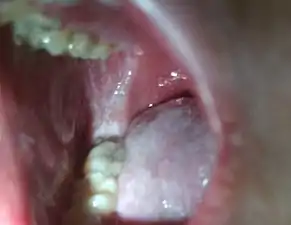

Koplik's spots seen inside the mouth are diagnostic for measles, but are temporary and therefore rarely seen.[28] Koplik spots are small white spots that are commonly seen on the inside of the cheeks opposite the molars.[27] They appear as "grains of salt on a reddish background."[30] Recognizing these spots before a person reaches their maximum infectiousness can help reduce the spread of the disease.[31]

Koplik's spots on the third pre-eruptive day

Koplik's spots on the day of measles rash